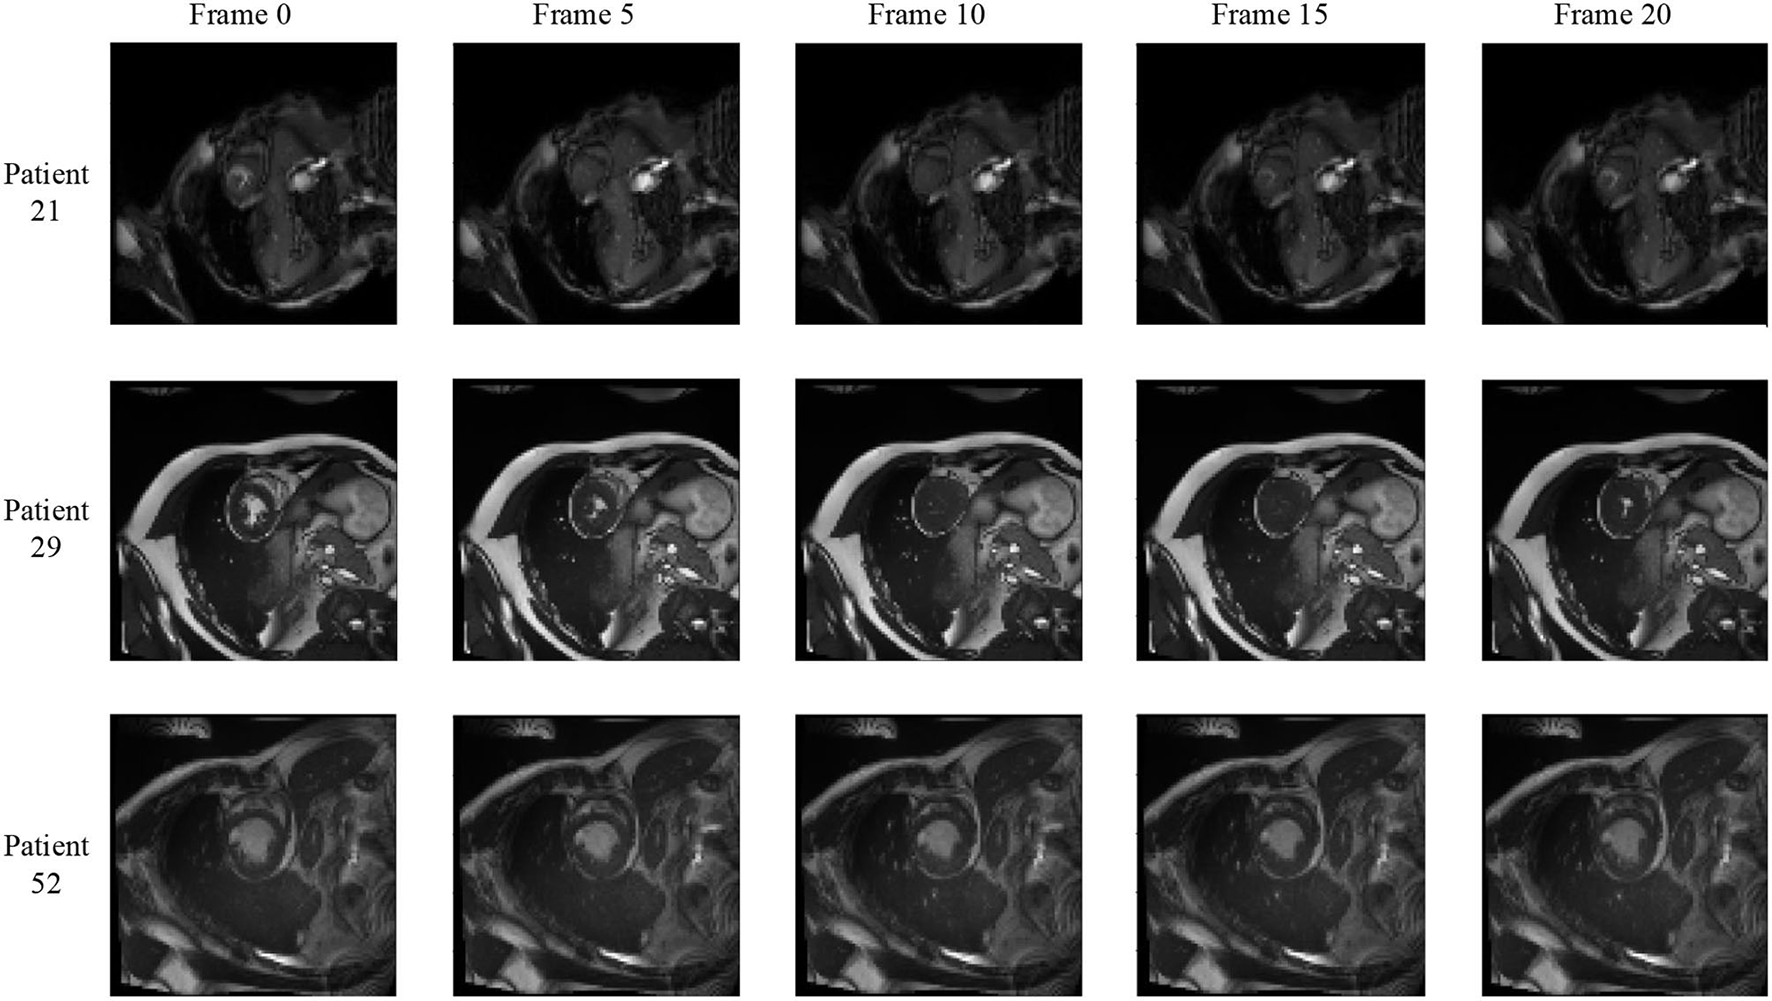

3.3. Bi-Directional Training

We notice that the prediction results of myocardium segmentation in the CMR image are highly related to the segmentation result of frames either behind or after it. The first frame of the CMR sequence will not receive enough information if we only use forward Conv LSTM. Figure 6 shows some frames of the CMR images of different patients in the ACDC dataset. We can see that the frames of CMR image of the last frame are highly related to the image of the next frame. Consequently, the prediction error of the first frame due to the brightness heterogeneity may propagate to the rest of the CMR frames.

Figure 6

Frames of CMR sequence from three patients. Note the brightness heterogeneity in left ventricular (LV) and right ventricular (RV) on the first few frames. Using LSTM in TCN, the model can get more temporal information from the previous and future frames and result in more accurate segmentation.